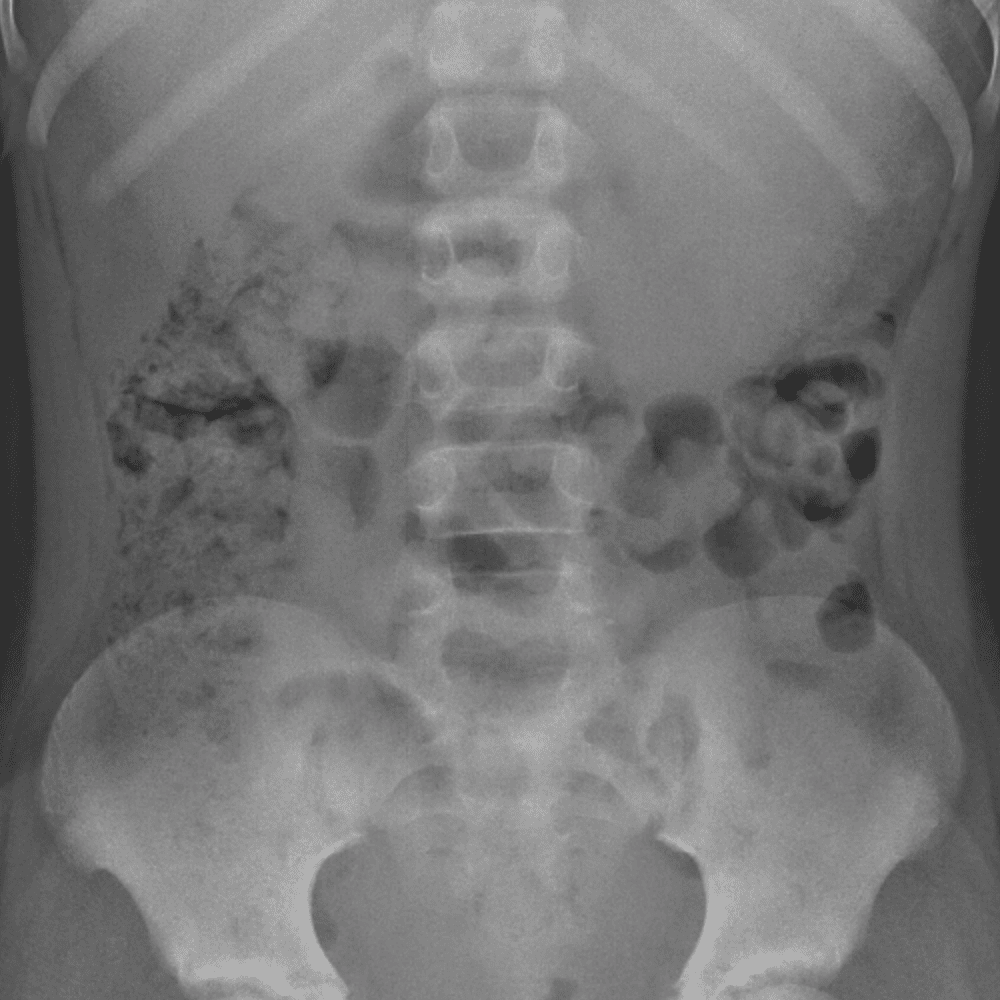

Peds Abdomen

Practice

Simulates call by including subtle or difficult cases and some normals.

30 cases